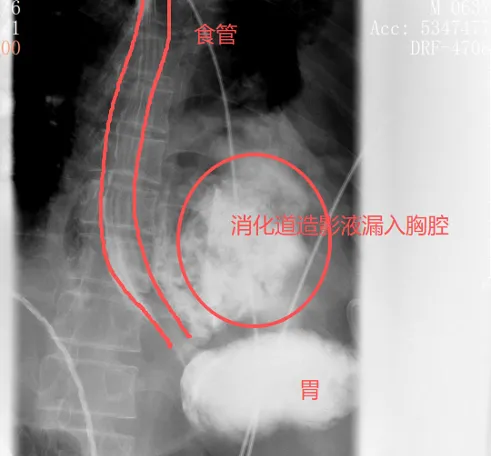

很快,口服钡餐的结果印证了他的判断:钡剂从食道下段的裂口处大量漏出,直接进入了左侧胸腔。

自发性食管破裂,也称为Boerhaave综合征,是胸外科最凶险的急症之一,发病急、进展快、死亡率极高。而此时,距离张叔发病还不到24小时——这是救治的黄金窗口期。

破裂后的场景是灾难性的。胃里的食物、强腐蚀性的胃酸和消化液,会顺着裂口直接漏进密闭的胸腔,在短时间内引发严重的胸腔感染,进展为脓胸、脓毒性休克。哪怕在医疗技术成熟的今天,这种情况的死亡率依然超过50%。